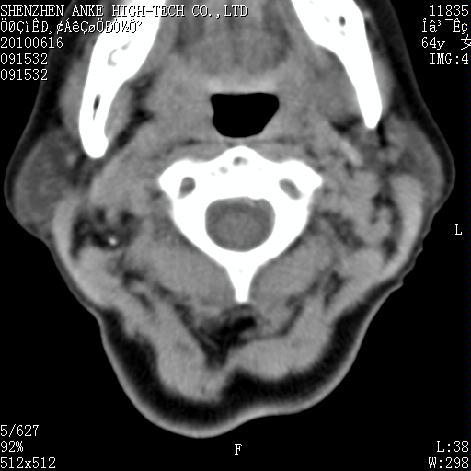

标题: CT27132:患者女,64岁,颈部及全身多处包块,现觉吞咽困难4 [打印本页]

标题: CT27132:患者女,64岁,颈部及全身多处包块,现觉吞咽困难4

右侧甲状腺占位,肿瘤可能性大,癌

右侧甲状腺癌伴右颌下腺淋巴结转移

右侧甲状腺癌伴淋巴结转移

右侧甲状腺癌伴淋巴结转移可能性大

右侧甲状腺癌伴淋巴结转移可能性大。